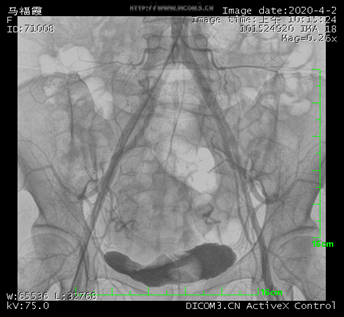

髂总动脉造影

数字减影血管造影机((Digital subtraction angiography,DSA),一般由X线发生装置、数字成像系统、机械系统、计算机控制系统、图像处理系统以及辅助系统等组成。DSA是通过电子计算机进行辅助成像的血管造影方法。它是应用计算机程序进行两次成像完成的,在注入造影剂之前,首先进行第一次成像,并用计算机将图像转换成数字信号储存起来,注入造影剂后再次成像并转换成数字信号,两次数字相减,消除相同的信号,得到一个只有造影剂的血管图像,这种图像较以往所用的常规血管造影剂所显示的图像更清晰、更直观,一些精细的血管结构亦能显示出来。

简单来说就是将造影剂注入需要检查的血管中,使血管显露原形。然后通过系统处理,使血管显示更加清晰,便于医生诊断或进行手术,这也是为什么DSA被称为“血管机”的原因。DSA的临床使用范围广泛,适用于心、脑、外周及各部位血管、肿瘤、泌尿、呼吸道以及其它消化道在内的各科室临床诊断和微创介入治疗。